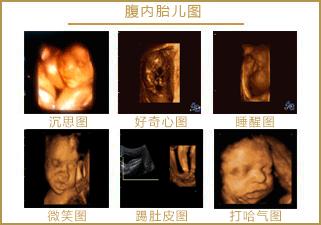

怀孕5个半月,胎儿已经有了面部表情,喜怒哀乐都会有,当然胎儿也会发笑。

5个半月的胎儿大脑发育趋于完善,能够控制感觉器官,使面部具有丰富的表情。感觉器官迅速分化,味觉、听觉、触觉、视觉、听觉等都在大脑中占据了一定的空间,神经元之间的连接也开始增加了。

5个半月的胎儿相当于22周,眼睛、鼻子、眉毛、耳朵、嘴巴等五官面貌结构完整,嘴巴、眉毛活动自如,面部表情丰富也很正常。

胎儿的听力能力进一步发展,对外界的声音极其敏感,当听到喜欢的音乐、妈妈温柔的声音时,胎儿会用微笑表示开心。所以,妈妈要多听一些美妙的音乐、多和宝宝说话,让宝宝感受到幸福,出生后也会笑得更美好。

从这里看出,在做四维彩超的时候很容易捕捉到胎儿的微笑,这时不要觉得奇怪,这是胎儿正常的生理反应。

胎儿还会哭会发怒

胎儿不仅会笑,还会发怒、还会哭。当他感到不舒服的时候,他会发怒,在肚子里乱踢,让妈妈感受到他的愤怒。

当他听到剧烈的声音时,比如吵架的声音、鞭炮的生意、杯子摔碎的声音,他会因为害怕而哭泣。只不过,他的哭声不是放声大哭,而是轻声地呜咽声,我们一般听不到这个哭声。